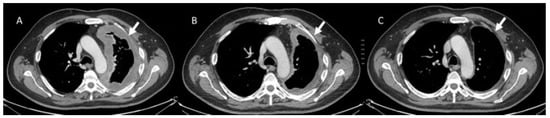

- Borcoman, E.; Kanjanapan, Y.; Champiat, S.; Kato, S.; Servois, V.; Kurzrock, R.; Goel, S.; Bedard, P.; Le Tourneau, C. Novel patterns of response under immunotherapy. Ann. Oncol. 2019, 30, 385–396. [Google Scholar] [CrossRef]

- Seymour, L.; Bogaerts, J.; Perrone, A.; Ford, R.; Schwartz, L.; Mandrekar, S.; Lin, N.; Litière, S.; Dancey, J.; Chen, A.; et al. iRECIST: Guidelines for response criteria for use in trials testing immunotherapeutics. Lancet Oncol. 2017, 18, e143–e152. [Google Scholar] [CrossRef]

- Kwak, J.J.; Tirumani, S.H.; Van den Abbeele, A.D.; Koo, P.J.; Jacene, H.A. Cancer immunotherapy: Imaging assessment of novel treatment response patterns and immune-related adverse events. Radiographics 2015, 35, 424–437. [Google Scholar] [CrossRef]